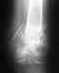

женщина 61 год, перелом шейки левого плеча со смещением. перелом был 14 ноября.Лечащий врач говорит что необходимо эндопротезирование плеча, но такие операции в городе где она лежит не делают (Нижегородская область). И насколько я слышал лечение пожилых людей консервативное.

Пока рука на косынке в лонгетке и с подвешенной гирей. Пальцу рук двигаются нормально.Посмотрите, пожалуйста, насколько необходимо ставить протез?В платных клиниках цена на такую операцию надо признать высока, может посоветуете куда можно обратиться по ОМС в Москве или Казани?Спасибо.

Эндопротезирование тут один из вариантов, можно сделать и остеосинтез. Лечение "по ОМС в Москве или Казани" представляется не сильно реальным. Получить от своего фонда ОМС направление в другой регион и гарантийное письмо по оплате мало кому удается.